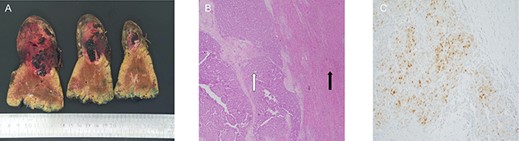

(A) macroscopic specimen demonstrating slices through a haemorrhagic lesion with normal liver parenchyma; (B) images demonstrating liver with intact architecture (black arrow) with HCC (white arrow) and (C) patchy nuclear staining with arginase-1 immunohistochemical stain.

Histopathological assessment revealed an 85-mm moderately differentiated HCC with evidence of vascular invasion that was completely excised with a 20-mm clear margin [TNM Staging (AJCC 8th edition): pT2] (Fig. 3). The patient’s recovery post-procedure was routine with transfer back to the rural hospital 13 days post-liver resection.